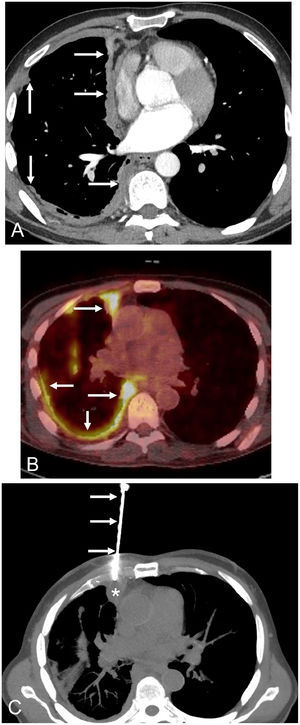

A) Axial thoracic CT image (mediastinal window) shows a solid nodular thickening (arrows) of the right hemithorax pleural surface that particularly involves the mediastinal pleura. B) Axial fused thoracic PET/CT image demonstrates an intense FDG uptake by the nodular pleural thickening (arrows). C) Axial chest CT image (mediastinal window) shows the biopsy needle (arrows) targeting the nodular pleural surface (asterisk).

The patient was a 59-year-old non-smoker male without known asbestos exposure, who complained of progressive dyspnea and low-grade fever. The patient was suffering from PV and had started treatment with ruxolitinib 17 months earlier. A chest radiograph showed a marked right lung volume loss with apical pleural thickening. A thoracic computed tomography (CT) revealed a striking nodular thickening of the right pleural surface that particularly involved the mediastinal pleura (Fig. 1A). There were no suspicious lung nodules, enlarged lymph nodes, or significant pleural effusion. A whole-body fluorine-18 fluorodeoxyglucose positron emission tomography/CT (FDG-PET/CT) demonstrated a markedly increased FDG uptake by the right hemithorax thickened pleural surface (Fig. 1B), but also showed additional foci of hypermetabolic activity involving the peritoneal surface and a single bone lesion in the T5 vertebral body. A presumed diagnosis of a metastatic pleural mesothelioma was made, and the patient underwent a percutaneous CT-guided pleural core-needle biopsy (Fig. 1C). Pathologic findings did not detect cancer cells but revealed extensive necrotizing granulomatous inflammation. Real-time polymerase chain reaction (PCR) for Mycobacterium tuberculosis was detected on one of the percutaneously-obtained specimens, and a final diagnosis of disseminated extranodal tuberculosis was made. The patient was started on four antituberculous drugs (isoniazid, rifampin, pyrazinamide, and ethambutol) and improved both clinically and radiologically.